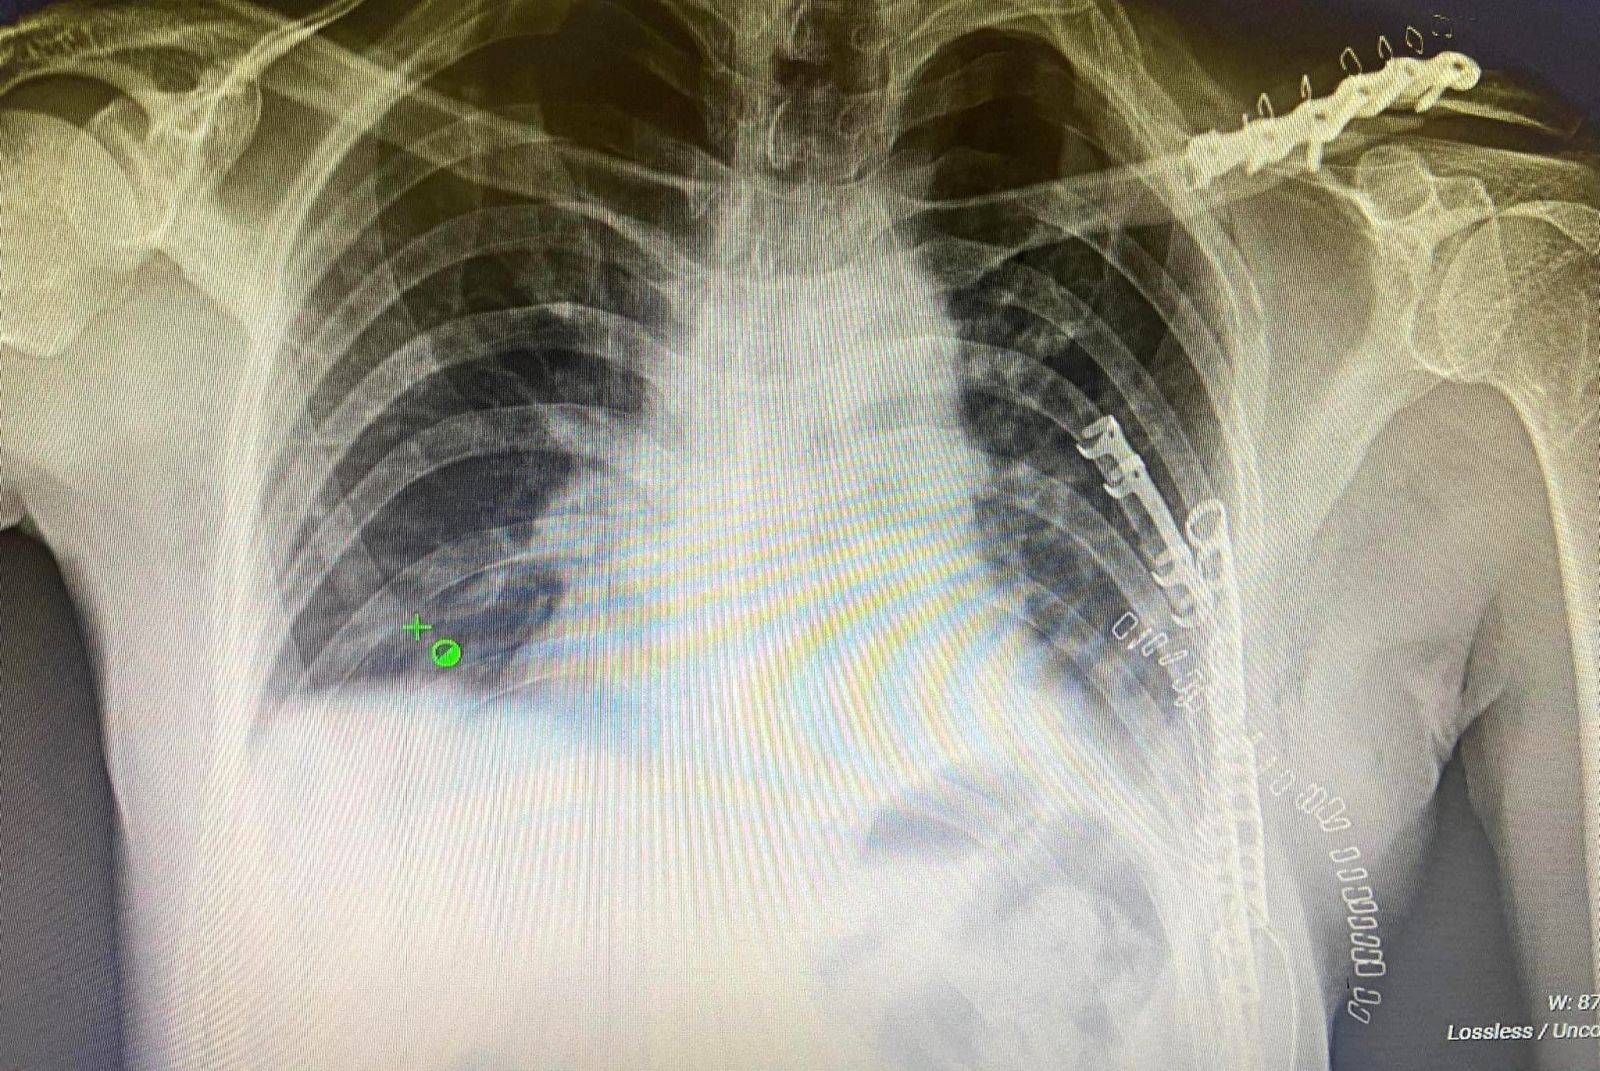

Гэмтэл согог судлалын үндэсний төвийн Хавсарсан гэмтлийн мэс заслын тасгийн эмч, мэргэжилтнүүд цээжний хөндийн битүү гэмтэл, олон хавирганы тогтворгүй хугарлыг бэхлэх мэс засал эмчилгээг эх орондоо нутагшуулан, эмнэлгийн тусламж үйлчилгээнд өдгөө 6 дахь жилдээ хэрэгжүүлэн ажиллаж байна.

Энэ хүрээнд алсын дуудлагын дагуу нийт 18 аймагт очиж яаралтай мэс засал хийснээс гадна орон нутгийн эмч мэргэжилтнүүдийг чадавхижуулах зорилгоор ажлын байран дээр нь сургалт явуулж, үзлэг оношлогоо болон мэс засал эмчилгээг хамтран хийж буй юм.

Тус ажлын үр дүнд Дорноговь, Говь-Алтай аймгийн нэгдсэн эмнэлгийн Гэмтэл, мэс заслын тасагт цээжний хөндийн битүү гэмтэл, хавирганы хугарлыг эмчлэх суурь багажтай болсноор энэ төрлийн мэс засал эмчилгээг орон нутагт амжилттай хийж эхэлжээ.

Цаашид цээжний хөндийн битүү гэмтэл, олон хавирганы тогтворгүй хугарлыг бэхлэх мэс засал эмчилгээг бусад аймагт нэвтрүүлэх, эмч мэргэжилтнүүдийг сургаж чадавхижуулахад анхаарч, ГССҮТ-ийн Хавсарсан гэмтлийн мэс заслын тасгийн хамт олон зорилтот томоохон ажлуудыг хийхээр төлөвлөсөн байна.